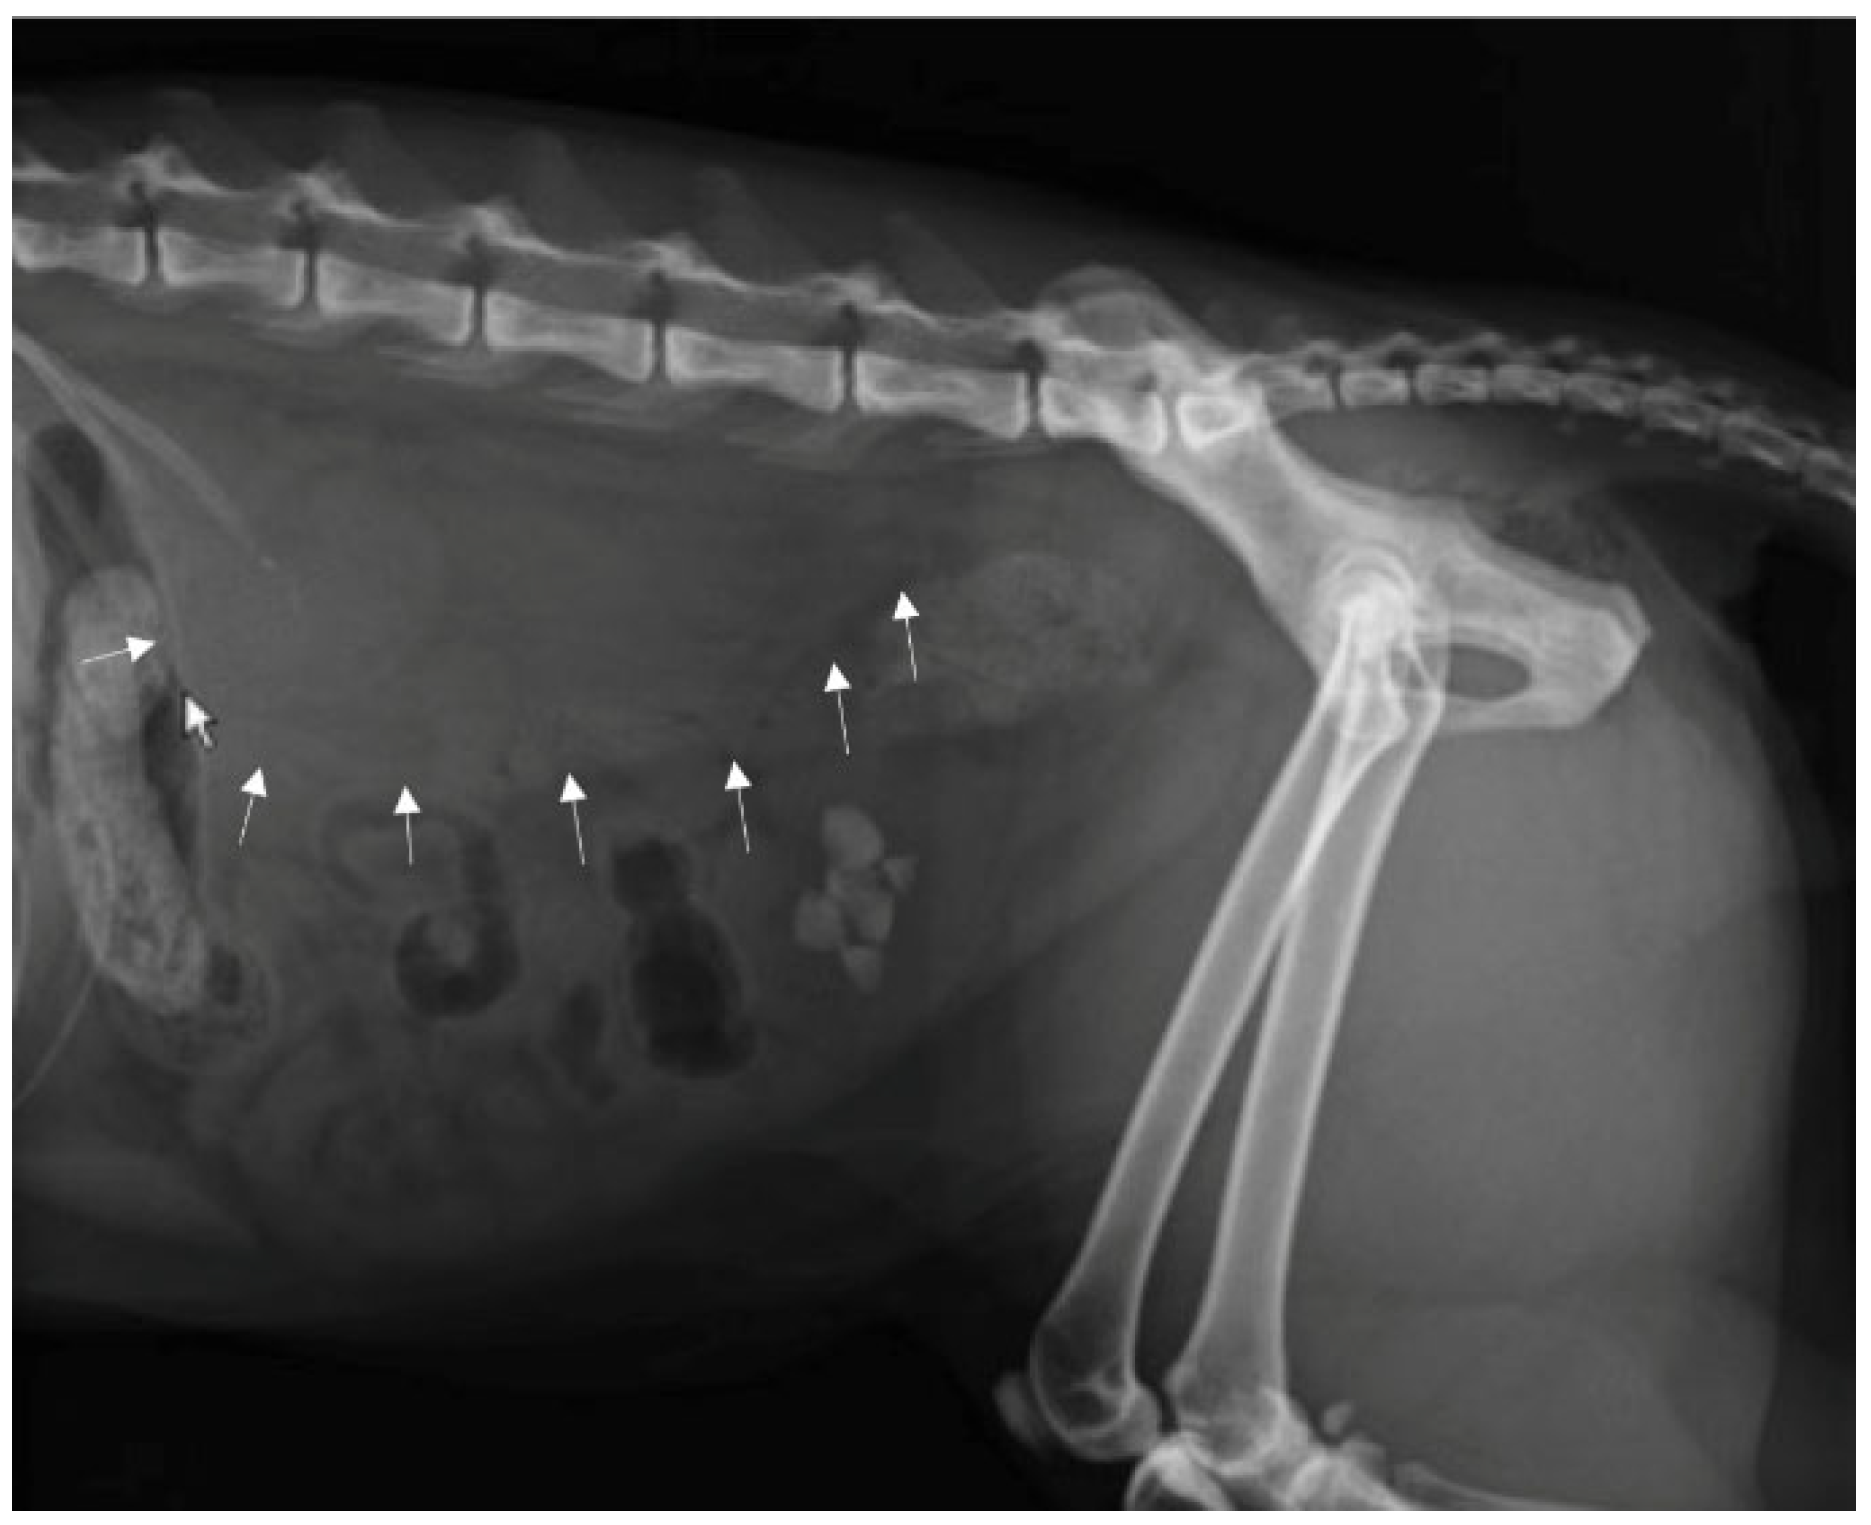

A direct radiographic study of the abdomen with orthogonal projections was performed, using a radiographic system (Morpheus, Gieffe Elettromedicali, Misterbianco (Catania, Italy) and a digital radiography system (Fujifilm Medical Systems, Milan, Italy). This examination showed a loss of soft tissue contrast in the lumbar region, and radiopaque stones in the urinary bladder (Figure 1).

Figure 1.

Lateral radiograph of the abdomen: loss of contrast in the lumbar region (arrows) and a presence of uroliths in urinary bladder.